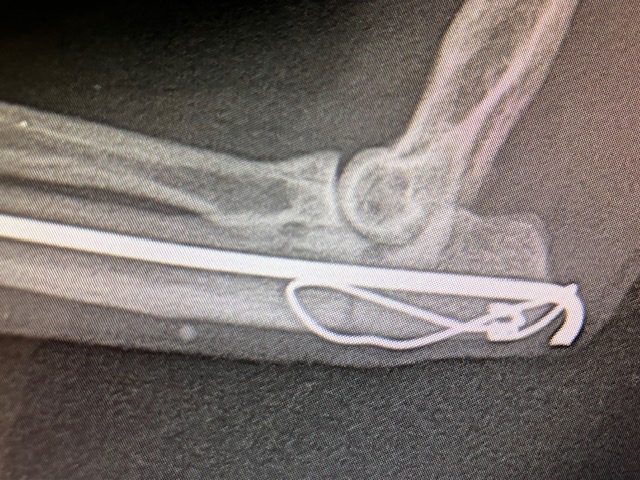

Nous abordons l’articulation du coude par voie latérale. Un clou de Steinmann de 1,2 mm est introduit par voie rétrograde dans le foyer de fracture, dans l’about proximal olécranien, puis repoussé dans la cavité médullaire de l’about distal de l’ulna sur la majorité de sa longueur. Cela permet de réduire la fracture et de mettre en compression les 2 abouts osseux.On prend des précautions pour ne pas trop léser le tendon du triceps brachial. La broche est courbée proximalement, pour éviter les lésions de la peau et permettre un retrait ultérieur de l’implant.

Pour augmenter la solidité, éviter que le foyer de fracture ne s’écarte, nous posons en complément un Fil de cerclage en 8, passant dans un orifice osseux percé dans l’about ulnaire distal puis s’accrochant sur l’extrémité courbée de notre broche, en passant sous le tendon du triceps. Cette technique de Haubanage met en compression le foyer de fracture et assure une contention supplémentaire, en limitant aussi partiellement les mouvements de rotation.